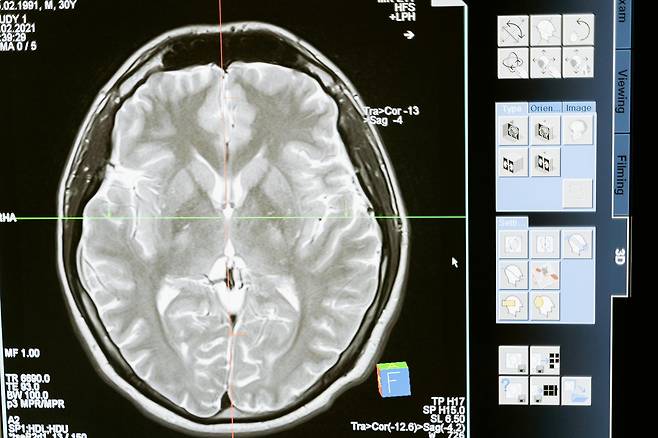

혈압도 정상인데 왜 뇌출혈이?

하지만 혈압 수치가 정상이라고 해서 뇌혈관이 안전한 건 아닙니다. 최근 연구에 따르면, 뇌출혈 환자 중 약 30%가 ‘정상혈압’ 판정을 받은 사람으로 밝혀졌습니다.